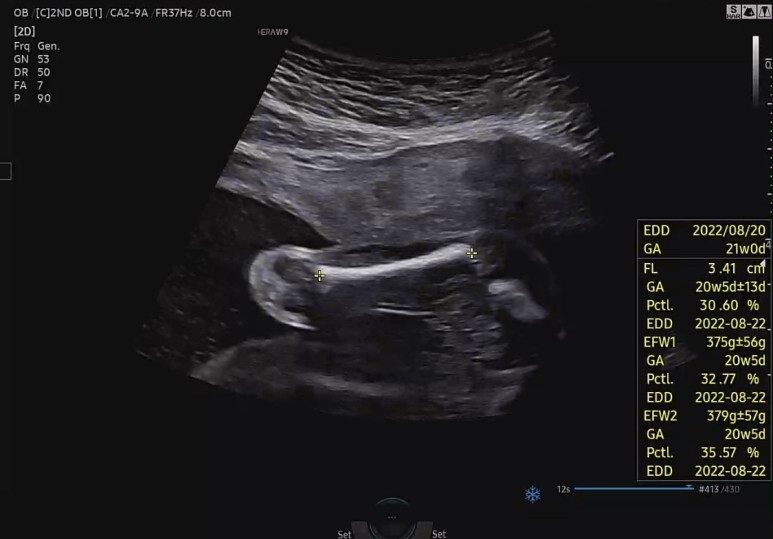

허벅지뼈 길이 확인 (FL)

전체적으로 무난히 잘 자라주고 있다. 평균보다 살짝 작지만 괜찮아 :)